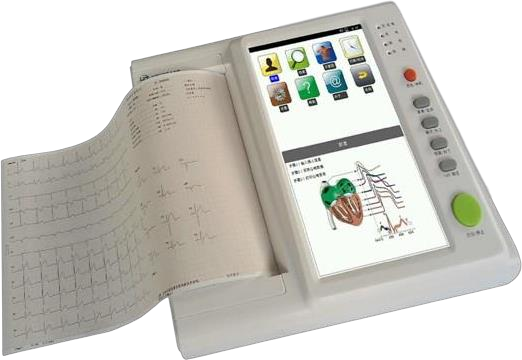

Bionet CardioTouch 3000 12 Channel ECG Machine

Bionet CardioTouch 3000 12 Channel ECG Machine

.jpeg) ECG 12 CHANNEL - MEDEXBIO

ECG 12 CHANNEL - MEDEXBIO

ECG MACHINE 6 CHANNEL - MEDEXBIO

ECG MACHINE 6 CHANNEL - MEDEXBIO

3 Channel ECG - MEDEXBIO

3 Channel ECG - MEDEXBIO

ECG MACHINE 12 CHANNNEL - INDIAN BRAND

ECG MACHINE 12 CHANNNEL - INDIAN BRAND

Digital 6 Channel ECG Machine

Digital 6 Channel ECG Machine

Yonker 7inch display 3 channel ECG Machine with touch screen

Yonker 7inch display 3 channel ECG Machine with touch screen

3 Channel 7 Inch Touch Screen Portable Electrocardiograph ECG Machine

3 Channel 7 Inch Touch Screen Portable Electrocardiograph ECG Machine

Zoncare 12 Channel ECG Machine

Zoncare 12 Channel ECG Machine

Edan ECG Machine SE-601 Series 6-Channel ECG

Edan ECG Machine SE-601 Series 6-Channel ECG

CONTEC ECG600G Digital 6 channel Electrocardiograph ECG machine EKG CE

CONTEC ECG600G Digital 6 channel Electrocardiograph ECG machine EKG CE

CONTEC ECG300G Electrocardiograph

CONTEC ECG300G Electrocardiograph

Yonker 7inch Display 3 Channel ECG Machine With Touch Screen

Yonker 7inch Display 3 Channel ECG Machine With Touch Screen

DAWEI 12Channel ECG Machine

DAWEI 12Channel ECG Machine

Dawei ECG Machine 3 Channel

Dawei ECG Machine 3 Channel

.jpeg) Comen – 12 Channel ECG Machine, CM1200

Comen – 12 Channel ECG Machine, CM1200

ECG 1200G – Contec

ECG 1200G – Contec

ECG 1212G – Contec

ECG 1212G – Contec

YKD MED ECG 3 CHANNEL

YKD MED ECG 3 CHANNEL

ECG 12 CHANNEL 3A CANADA

ECG 12 CHANNEL 3A CANADA